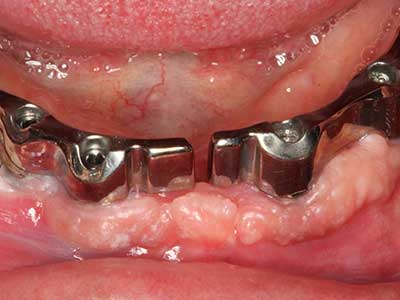

Sollen chirurgische Eingriffe mit unmittelbarer Knochenbeziehung an empfindlichen Strukturen wie Blutgefäßen oder Nerven erfolgen, so bergen rotierende Instrumente ein erhebliches Potential an iatrogener Schädigung. Gerade bei Nervdarstellungen nach iatrogener Schädigung, oder aber im Zuge einer Nervlateralisation für resektive und rekonstruktive Eingriffe oder Implantatinsertionen können piezoelektronische Geräte hilfreich sein Knochendeckel zu präparieren und nervnahe Hartgewebsanteile zu entfernen (Abb. 17-20). Ein leichter Kontakt des Nervstrangs zur Piezospitze bleibt dabei in der Regel folgenlos – allerdings kann eine unvorsichtige Vorgehensweise mit sägeartigen Bewegungen bzw. Ansätzen bei noch vorhandener knöcherner Unterlage durchaus temporäre oder aber auch permanente Nervschädigungen verursachen. Das Risiko einer solchen Schädigung wird jedoch als wesentliche geringer eingeschätzt als unter Anwendung von Säge- oder Fräsinstrumenten (Pereira, Gealh et al. 2014).

Indikation: Nervnahe Präparation

Wie bereits erwähnt lassen sich auch im Bereich der chirurgischen Zahnerhaltung Indikationsgebiete für die Piezochirurgie finden. Durch die Verwendung von speziellen Arbeitsspitzen wird die Darstellung der Wurzelspitze erleichtert, und gerade im unteren Prämolaren- und oberen Seitenzahnbereich lassen sich Nerven und Kieferhöhlenschleimhäute einfacher schützen. Bei undichtem apikalen Abschluss präparieren abgewinkelte Diamantspitzen zielgenau die Resektionskavität für das retrograde Wurzelfüllmaterial. Die Spitzen können durch die Ultraschalltechnik sehr grazil gestaltet sein, was Übersicht und Größe der Zugangskavität verbessert. So gehört in dieser Indikation die Anwendung der Ultraschallchirurgie zu den Standardverfahren der Wurzelspitzensresektion (Del Fabbro, Tsesis et al. 2010, Scarano, Artese et al. 2012).